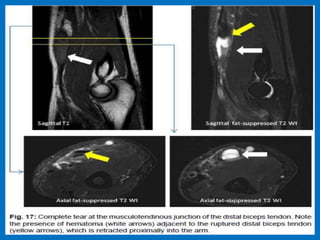

Short head (white arrow). Note the presence of fluid signal filling the tendinous gaps.

Findings are far more conspicuous in the FABS position.

Biceps tendon tear.

Complete tear of distal biceps tendon.